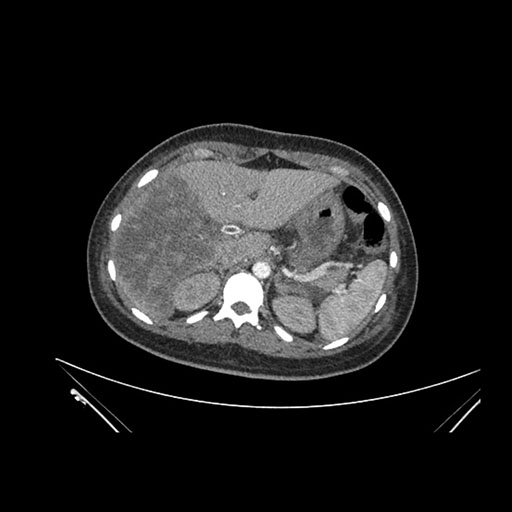

Imaging Analysis

Look through the patient's CT scan to identify any areas of concern for the necessary procedure.

Axial Venous

Based on initial findings, which issue(s) would you be most concerned about?